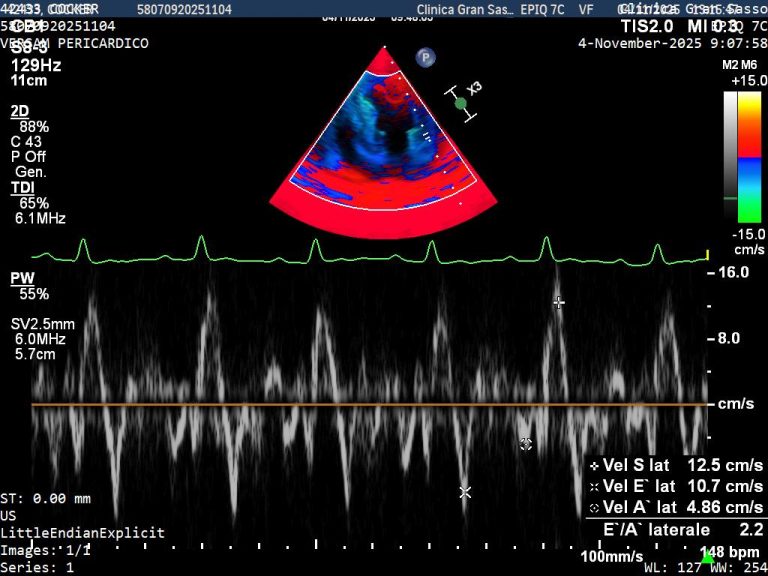

Cardiology Referral Centre

Our cardiology service is led by Dr. Emi Capurro ultrasonographer with advanced training and a Postgraduate Certificate in Small Animal Cardiology. The service is dedicated to diagnosis, staging and management of cardiovascular disease in companion's animals.